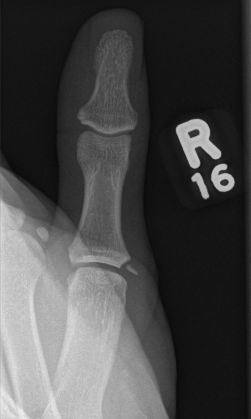

thumb

Thumb Radial Collateral Ligament

Gamekeeper's Thumb

Injury to ulnar collateral ligament of thumb MCPJ